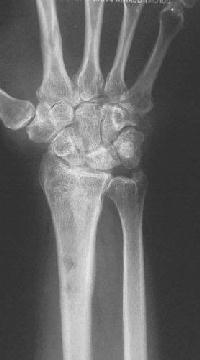

Clinical Example: Distraction plate fixation of distal radius fracture

A tricky case, for the patient previously had a large skin graft over the dorsal metacarpus / wrist / forearm. Incisions are marked here just before the plate was removed.

distal radius fracture

distraction plate